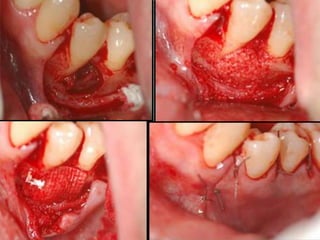

• #18 a)  Intrabony osseous defect before cyst enucleation. b) Following debridement, decortication and allograft placement. C) Collagen membrane adaptation. D)  Primary flap closure using 5.0 Dacron suture.